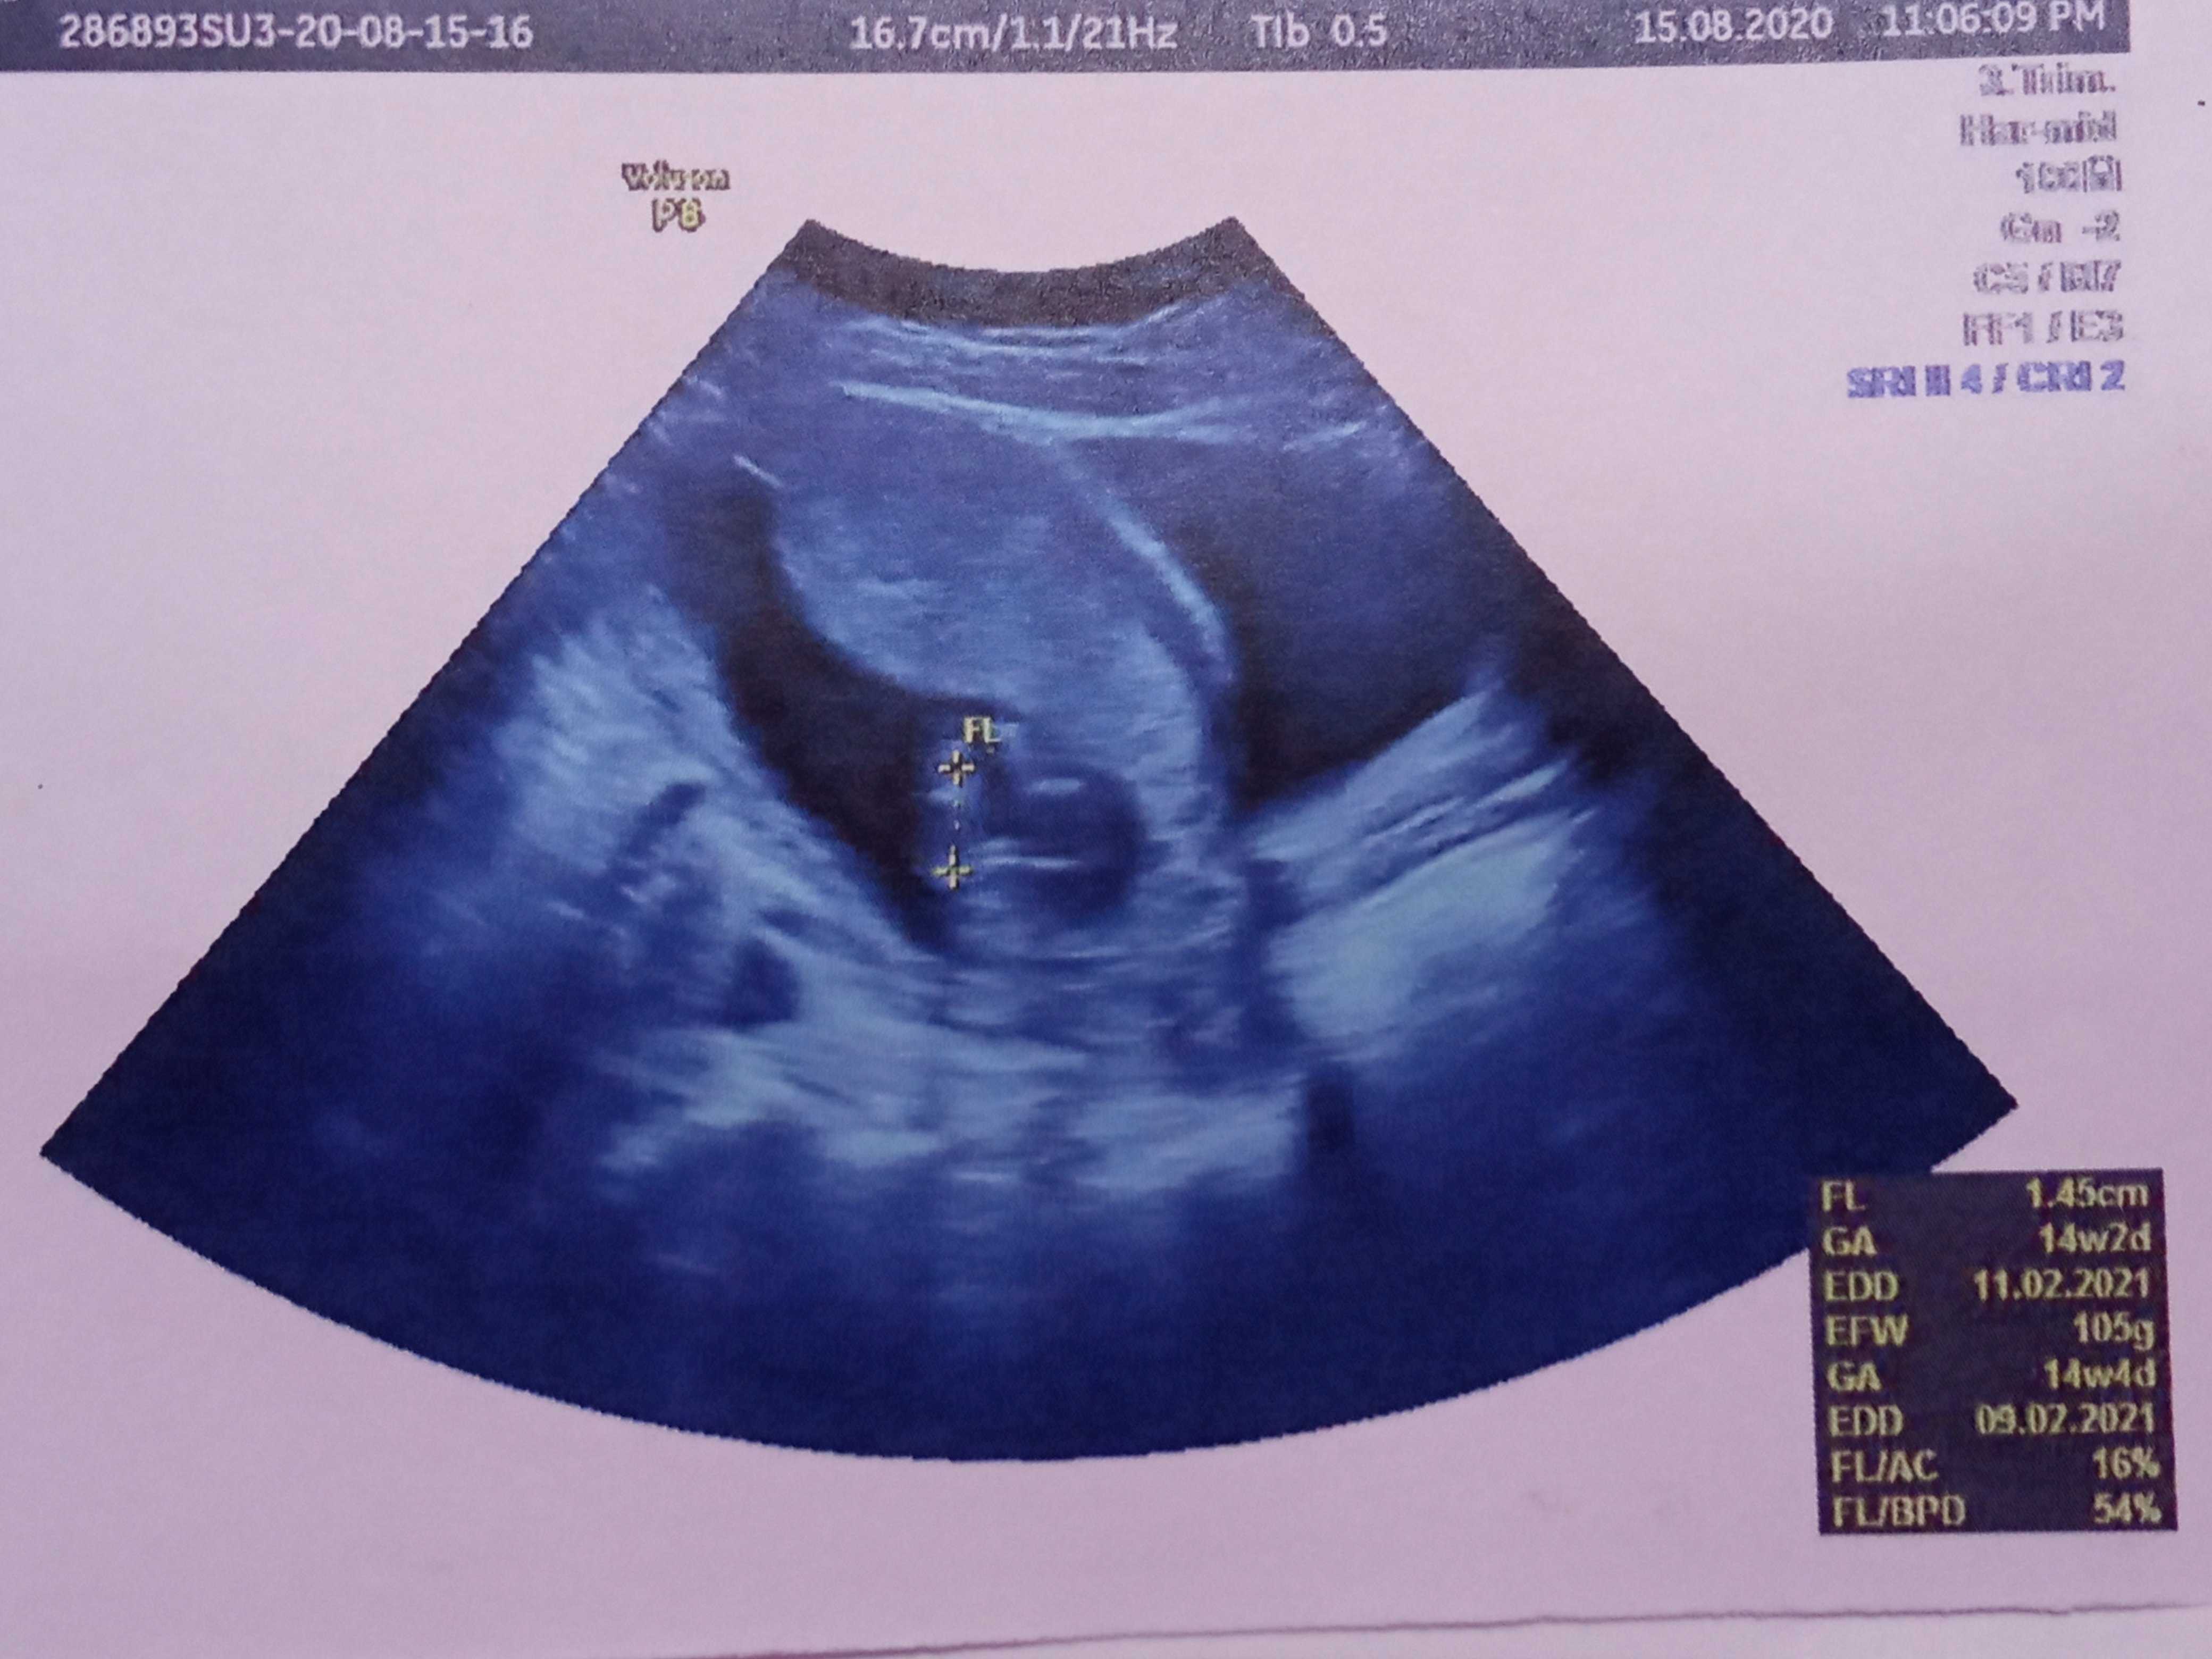

انا سويت سونار وابغى اعرف كم طول عنق الرحم؟ وهل يحتاج ربط او لا ؟ انا حامل في الاسبوع 21